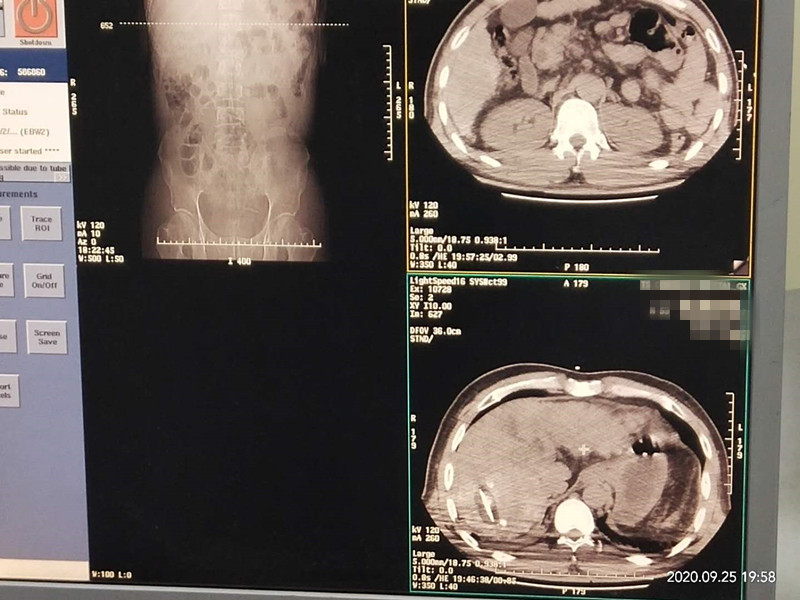

53岁患者肝部氩氦刀冷冻消融